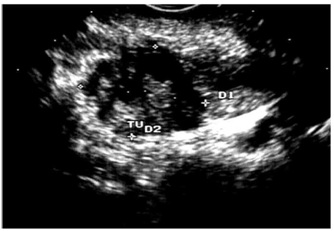

2.על-שמע (אולטרהסאונד) — בחולים הלוקים בשאתות בלבלב אפשר להדגים את השאת, וכן לראות את דרכי המרה (תצלום 23.9).

האולטרה-סאונד האנדוסקופי (EUS) מאפשרת לראות את השאת, את גודלה (איור 24.9);

האם פרצה לאיברים אחרים, תפסה כלי דם או מערבת בלוטות לימפה (תצלום 25.9).